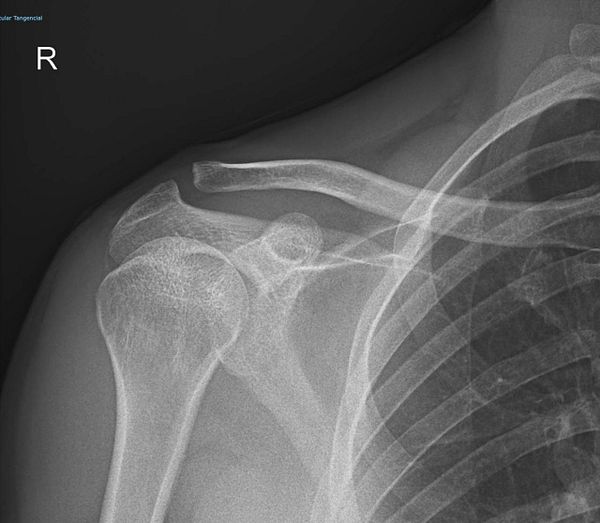

See x-ray photos of right shoulder #life